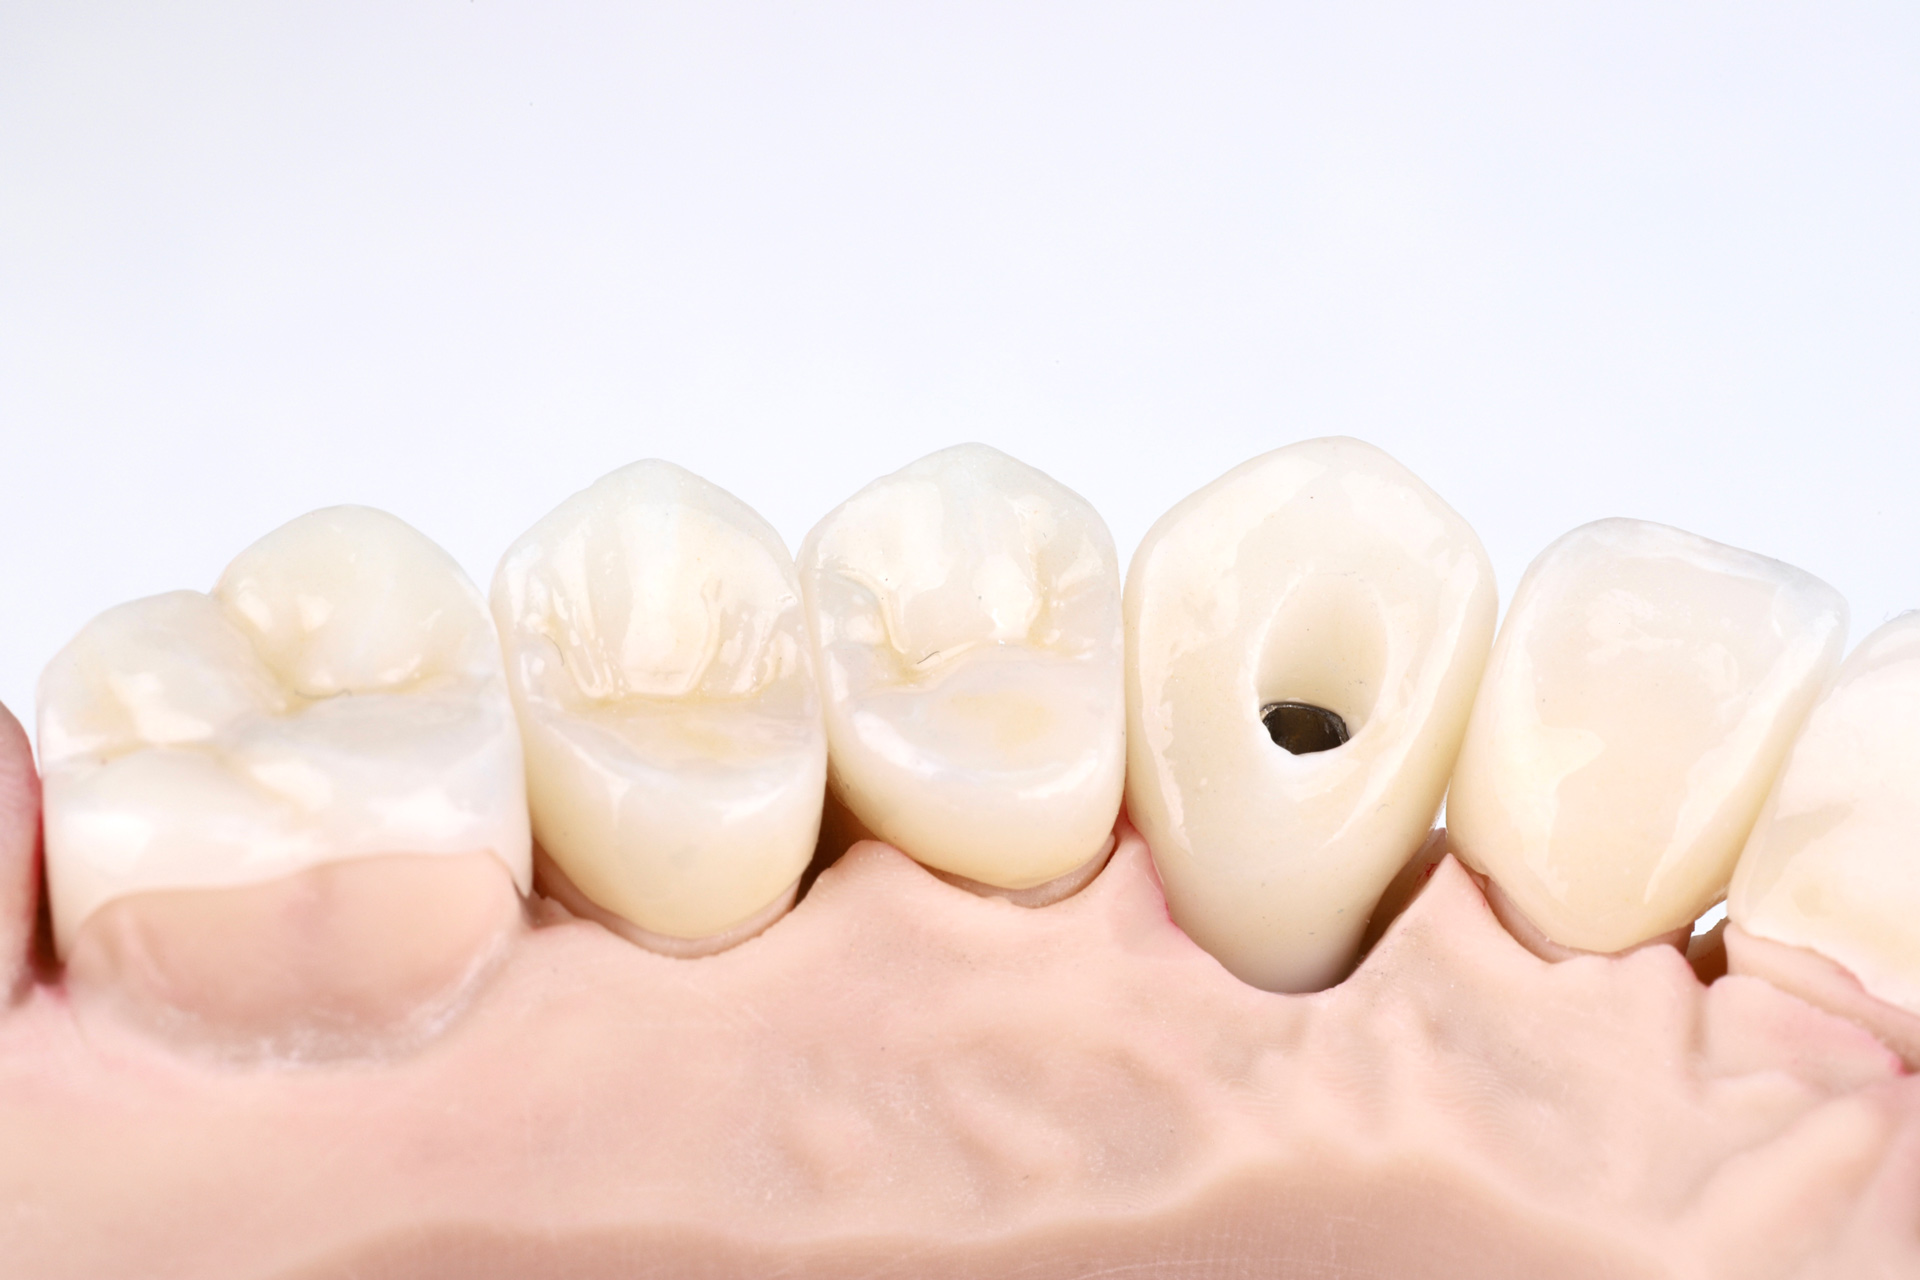

Лесі порекомендував звернутись до мене її лікуючий стоматолог з приводу корекції естетики усмішки. Після планування та обговорення всіх деталей ми встановили імплантант в естетичній зоні. Згодом змоделювали індивідуальну форму та обрали пропорції нових керамічних вінірів.